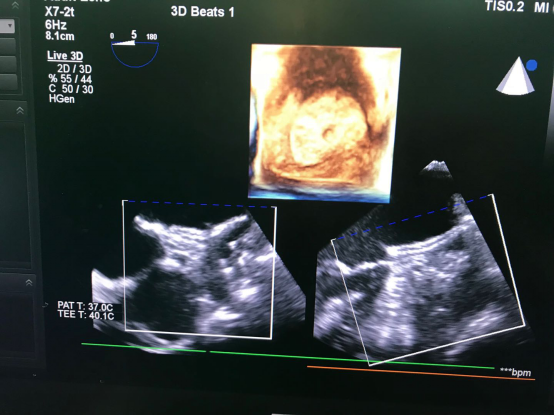

▲左心耳封堵器成功释放后经食道三维超声心动图像

六院心血管外科励峰主任团队最终决定为她实行“胸腔镜辅助下房颤射频消融+完全经食道超声引导下经皮经股静脉左心耳封堵术”,这是一次“一站式手术”,一次手术解决多个问题。它突破了常规在X射线下的操作,保护了病人,也保护了手术医生,实现“零射线、零造影剂”,也相应减少了患者的医疗费用与负担。